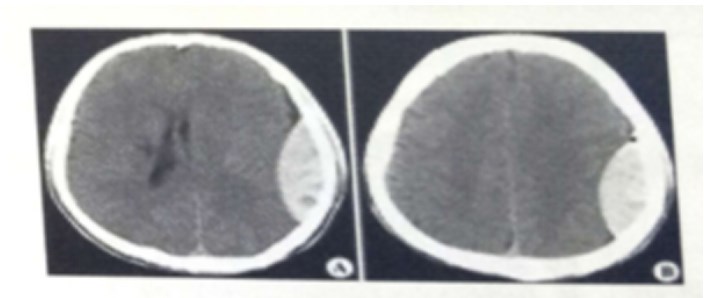

试题:男,44岁。头部外伤12小时。结合CT片,此诊断为(2分)

A.硬膜下血肿

B.脑出血

C.硬膜外血肿

D.颅骨骨折

答案:C